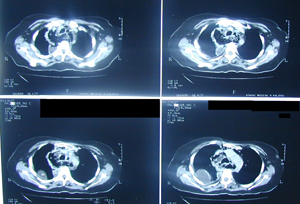

Εικόνα 2α-δ

Αξονική τομογραφία θώρακος σε διαφορετικά επίπεδα. Αναδεικνύει τα ίδια ευρήματα με την απλή ακτινογραφία και θέτει την διάγνωση της ρήξης της τραχηλικής μοίρας του οισοφάγου με εικόνα εμπυήματος του δεξιού ημιθωρακίου και εικόνα μεσοθωρακίτιδας με υδραερικό επίπεδο τόσο στο μεσοθωράκιο όσο και στον τράχηλο.